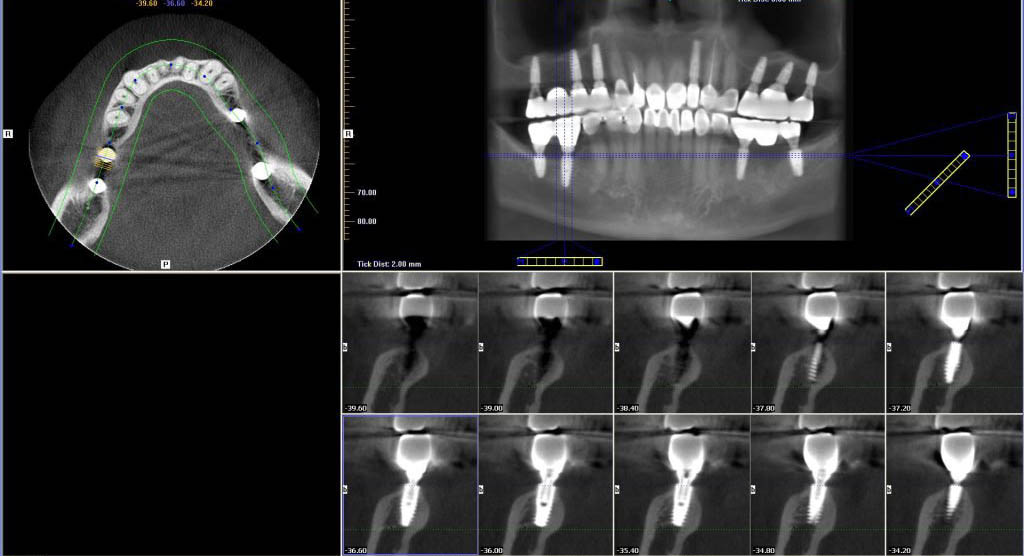

Chụp CT để xác định chính xác tình trạng răng miệng và xương hàm

Trước khi diễn ra ca phẫu thuật, khách hàng được bác sĩ kiểm tra và chụp CT để biết được tình trạng, mật độ xương cũng như chiều cao xương và răng của khách hàng, từ đó nhận biết được khách hàng có đủ điều kiện để thực hiện trồng răng Implant hay không? Nếu kích thước của hàm hạn chế khách hàng có thể sẽ phải nâng xương hoặc ghép xương trước khi thực hiện trồng răng Implant.

Hình ảnh CT răng

Ngoài ra, sau khi chụp CT xong, để đảm bảo sức khỏe, bác sĩ hoặc điều dưỡng sẽ vệ sinh khoang miệng và điều trị dứt điểm các bệnh lý về răng miệng của khách hàng. Vì vậy, đây được xem là bước bắt buộc phải thực hiện trước khi khách hàng bước vào quá trình thực hiện trồng răng Implant.